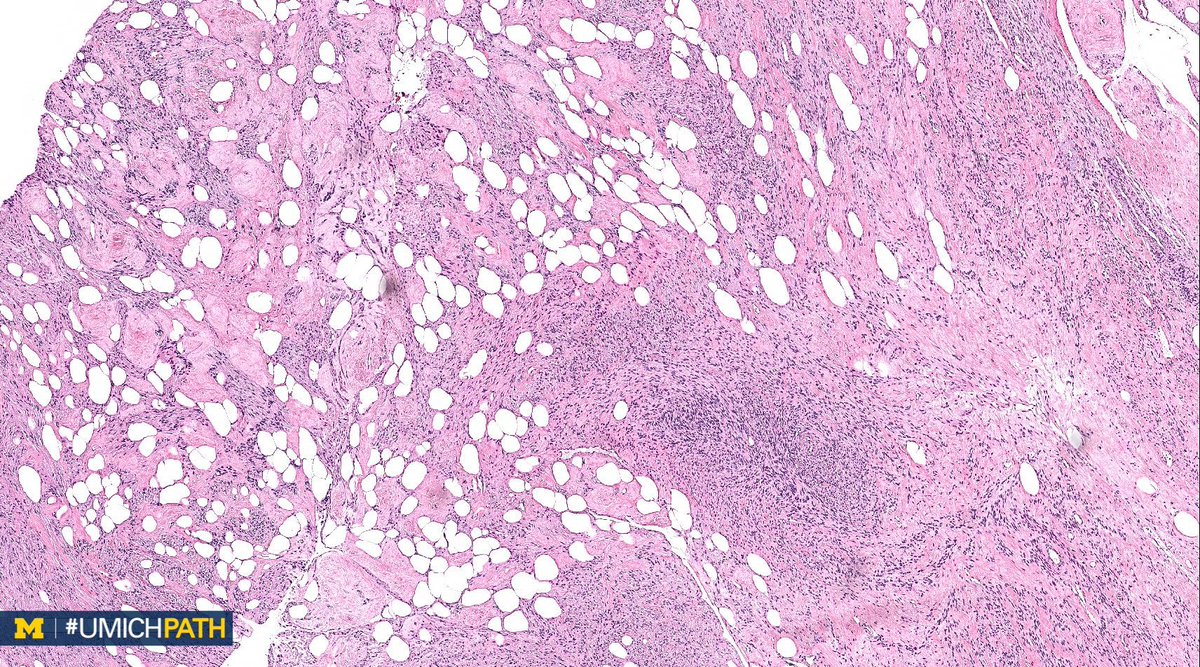

A: Lipoleiomyoma. A variant of uterine leiomyomata. Gross: Well circumscribed mass with alternating yellow and white areas. Histo: Variable admixture of bland smooth muscle cells and adipocytes. Very rarely can have glandular elements (adenolipoleiomyoma). #GYNPath #DailyDx